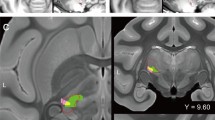

While significant shifts in the eccentricity of an individual brain region reflect alterations in its overall connectivity pattern, this metric does not clarify which specific aspect of its connectivity has undergone change. That is, although changes in eccentricity are indicative of a change in how a brain region functionally interacts with other areas, it does not reveal the precise nature of these connectivity alterations. To address this particular question, we conducted seed connectivity analyses to detail the pre- to post-stroke connectivity alterations for representative brain regions—in the PCC, OFC—that had demonstrated notable increases in eccentricity. For each region, we performed paired t-tests on the seed connectivity maps between pre- and post-stroke (i.e., Post > Pre), which produced contrast maps for each seed region (Fig. 3D). Note that in order to illustrate the full pattern of connectivity changes that underlie the eccentricity effects (as eccentricity is a multivariate measure), we elected to simply show the unthresholded contrast maps.

For the right PCC seed region, associated with the DMN, we observed the most prominent post-stroke increases in connectivity with bilateral posterior and mid cingulate regions, as well as several frontal regions of the DMN (Fig. 5, left). By contrast, the most prominent post-stroke decreases in connectivity for the PCC were observed with the left DLPFC of the frontoparietal Control network and right subgenual cortex of the limbic network. Together, these results suggest that the post-stroke manifold expansion of the PCC arises from its increased connectivity with several other DMN areas (i.e., segregation of the DMN) and relatively decreased connectivity with other distributed brain networks.

Representative changes in functional connectivity for seed regions that exhibited the largest changes in eccentricity from pre- to post-stroke (see Fig. 3D). Selected seeds are shown in yellow and are also indicated by arrows. Positive (red) and negative (blue) values show increases and decreases in connectivity, respectively, from Pre- to Post-stroke.

For the right subgenual cortex seed region, associated with the limbic network, we observed the most prominent post-stroke increases in connectivity with bilateral orbitofrontal cortical regions of the limbic network (Fig. 5, middle). By contrast, the most prominent post-stroke decreases in connectivity were observed with the bilateral medial posterior and mid-cingulate cortical regions, and sensorimotor cortical regions more broadly. Consistent with the results of PCC above, these results suggest that the post-stroke manifold expansion of subgenual cortex results from its increased connectivity with other limbic areas (i.e., segregation of the limbic network) and its decreased connectivity with other brain networks.

Finally, for the left medial frontal pole, located in the DMN, we found that this region exhibited its most prominent post-stroke increases in connectivity with bilateral frontal regions. (Fig. 5, right). By contrast, its most prominent decreases in connectivity were observed with left sensorimotor regions and right medial and lateral ventrotemporal regions of the visual network. Consistent with above, these results suggest that the post-stroke manifold expansion of medial frontal pole results from its increased connectivity with other medial frontal regions (i.e., segregation of DMN) and its decreased connectivity with other networks.